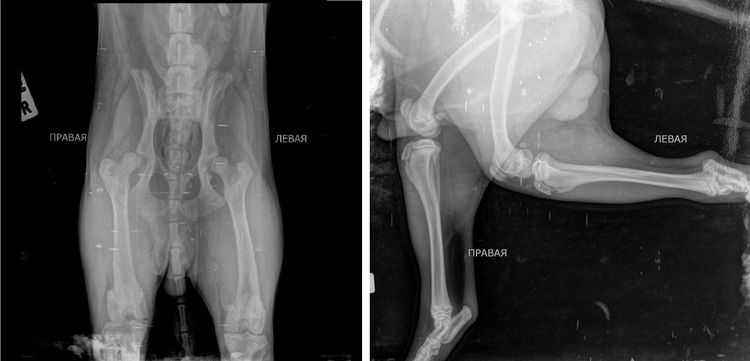

La notice d'utilisation fournit des recommandations précises concernant l'utilisation de X-GIA chez le chien. Ce produit est couramment utilisé pour traiter les affections suivantes :

- dysplasie de la hanche ;